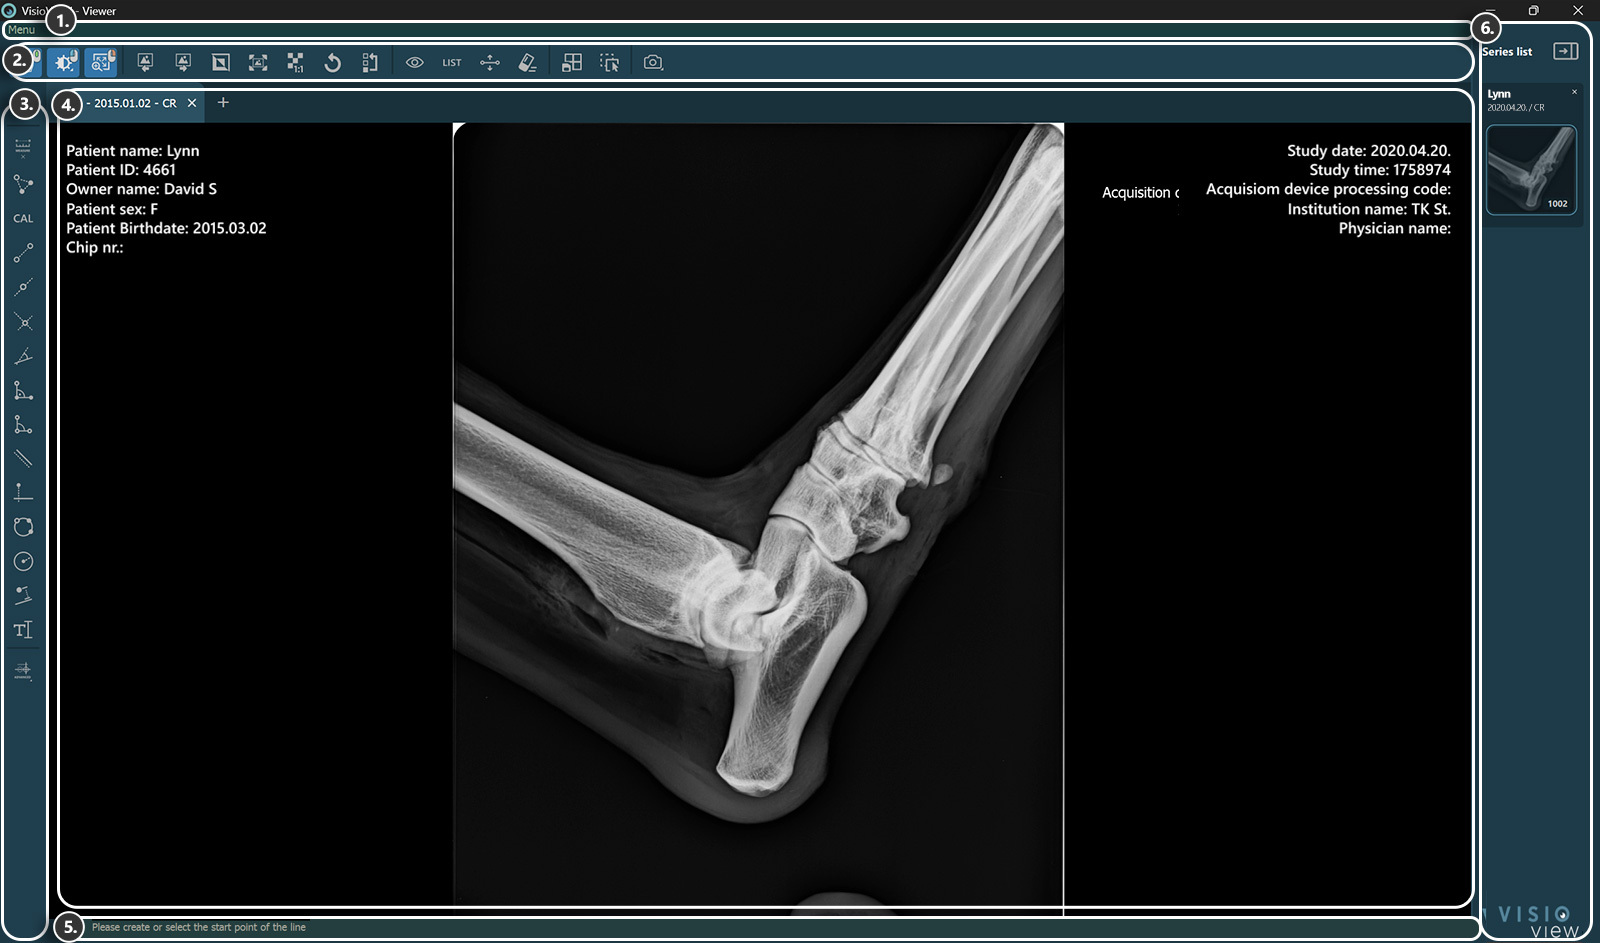

Sections of the VisioVIEW Viewer¶

The VisioVIEW Viewer consists of several sections, each tailored to a specific purpose. Below is a detailed description of each section.

Viewer Area¶

Patient information

Study information

Information Bar¶

Shows information or instructions about the currently selected tool.